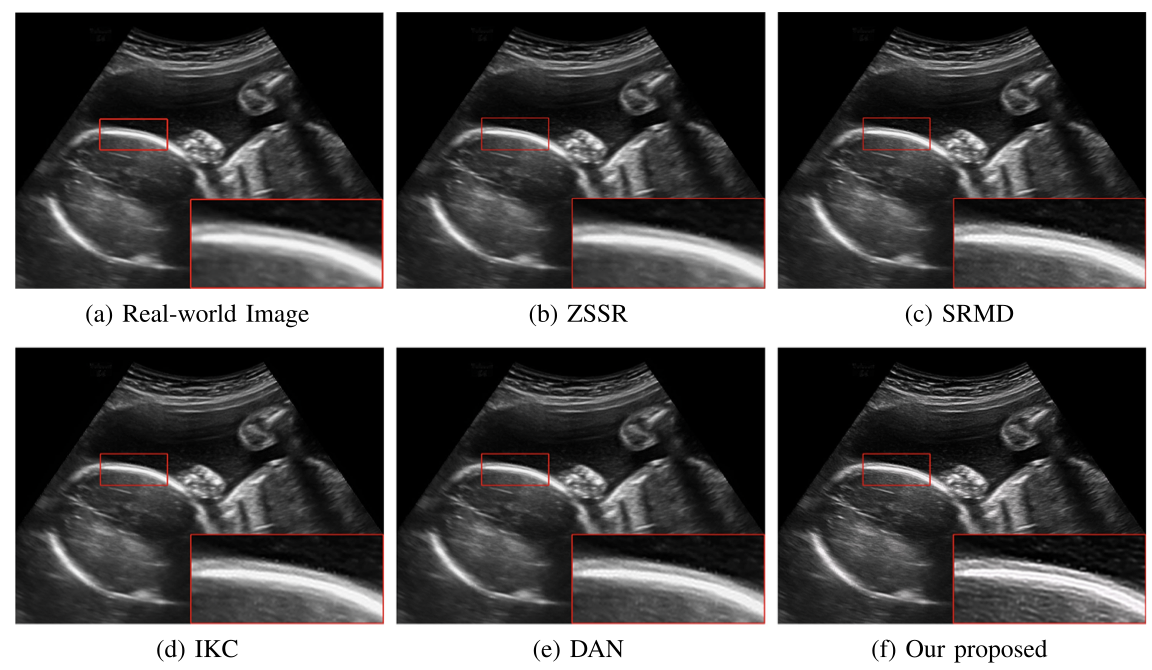

对于超声临床诊断而言,超声影像超分辨(ultrasound image super-resolution)可以提高超声成像质量,从而提高疾病诊断的准确性。但由于传感设备和传输介质的差异,实际场景中超声成像其退化模糊过程是未知且不可控的。为了解决未知退化场景超声医学影像准确超分辨的难题,团队提出了一种有效的基于退化模糊自估计且结合渐进残差学习和记忆提升机制的超声影像盲超分方法,初步实现了真实场景超声影像准确超分辨。相关研究成果发表在人工智能、计算机医学信息交叉领域一区TOP期刊《IEEE Journal of Biomedical and Health Informatics》(IF: 7.7)。公司为论文第一完成单位,BG大游平台刘恒教授、硕士生刘建勇分别为论文第一、第二作者。

(真实场景超声影像盲超分效果对比图)